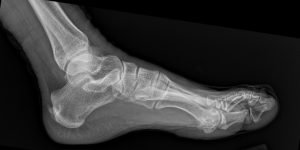

Fig. 2 Lateral view of the foot

Fig. 4 Annotated lateral foot x-ray showing soft tissue swelling over the dorsal forefoot.